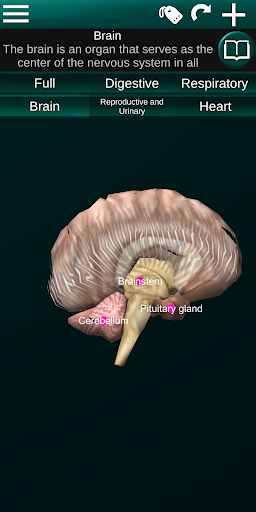

Toont een 3D-anatomisch model van de belangrijkste organen van het menselijk lichaam en een beschrijving van elk orgaan.

* Hersenen, waaronder de hersenen, het cerebellum en de hersenstam vallen.

* Gemakkelijk te openen en te navigeren (zoom, 3D-rotatie).

* Verberg of toon informatie.

* Beschrijvingen van elk orgel.